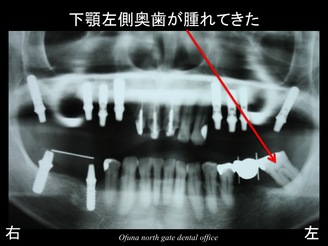

この時点で下顎左側の奥歯が腫れてきました。

初診時にすでにこの部分は、抜歯が必要なことをお話してあったため、この後抜歯となりました。

抜歯後には以下のような治療計画になりました。